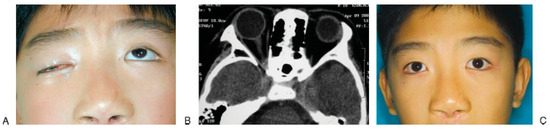

On the other hand, steroid therapy may be beneficial in patients with SOFS caused by edema from craniofacial fracture [28]. Postma et al. first reported the short-term use of dexamethasone (4 mg every 6 h) in patients with traumatic SOFS caused by zygomaticomaxillary complex fracture and sphenoid fracture. This patient was free from neurologic and ocular symptoms at the 3-month follow-up [28]. Similar medical treatment with loading dose of 1 mg/kg dex- amethasone followed by 0.5 mg/kg every 6 h was reported by Rohrich et al. [22] to treat SOFS in addition to the reduction of associated facial fracture. Recently, Acartu¨ rk et al. [24] reported excellent outcome in five patients with traumatic SOFS using megadose steroid of 30 mg/kg methylprednisolone followed by 5.4 mg/kg per hour for 48 h. All of them recovered completely by 6 months without any complications attributed to high-dose steroid. The literature on steroid treatment of traumatic SOFS is compressively reviewed [22,23,24,28,34], in which 7 (70%) of 10 cases of traumatic SOFS resolved completely after steroid treatment (Table 1). It seems that the patients treated with steroids have a better chance of neurologic recovery than those with observa- tion alone (70% versus 42.1%). Currently, the authors administer megadose steroid with methylprednisolone (30 mg/kg intravenous loading dose followed by 15 mg/ kg every 6 h for 3 days) to help reduce the swelling that may worsen the symptoms of SOFS, if there is no contraindication of using steroid in the injured patients (Figure 5).

Figure 5.

A 12-year-old boy fell down from a height that resulted in right periorbital trauma and superior orbital fissure syndrome (SOFS). (A) Palpebral ptosis and ophthalmoplegia were present. (B) Computed tomography (CT) showed a retrobulbar hematoma around the orbital apex. (C) View of patient revealing the functional recovery of the right eye 4 months after steroid treatment.